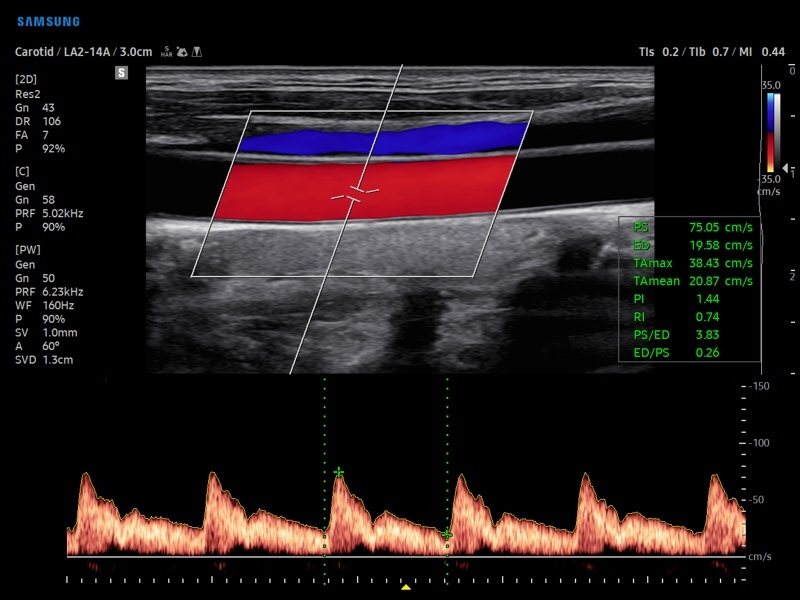

• Модуль AutoIMT - автоматическое вычисление комплекса интима-медиа общей сонной артерии (Intima Media Thickness). Данная оценка имеет большое значение для ранней диагностики атеросклероза и оценки риска развития инсульта и инфаркта миокарда.

• Модуль 2D Arterial Analysis программа, позволяющая автоматически провести анализ толщины и эластичности стенок разных участков сонной артерии, с выведением результатов в графической форме в движении (кинопетле) аналогично программе Strain для эхокардиографии.

• Сонные артерии:автоматическая, полуавтоматическая, ручная трассировка доплеровского спектра; ПСС, КДС, %СтПлощ, %Ст Диам, площадь сосуда, диаметр сосуда, средняя толщина интимы, объемный кровоток.

• Артерии верхних конечностей:автоматическая, полуавтоматическая, ручная трассировка доплеровского спектра; ПСС, КДС, %СтПлощ, %Ст Диам, площадь сосуда, диаметр сосуда, объемный кровоток.

• Артерии нижних конечностей:автоматическая, полуавтоматическая, ручная трассировка доплеровского спектра; ПСС, КДС, %СтПлощ, %Ст Диам, площадь сосуда, диаметр сосуда, объемный кровоток.